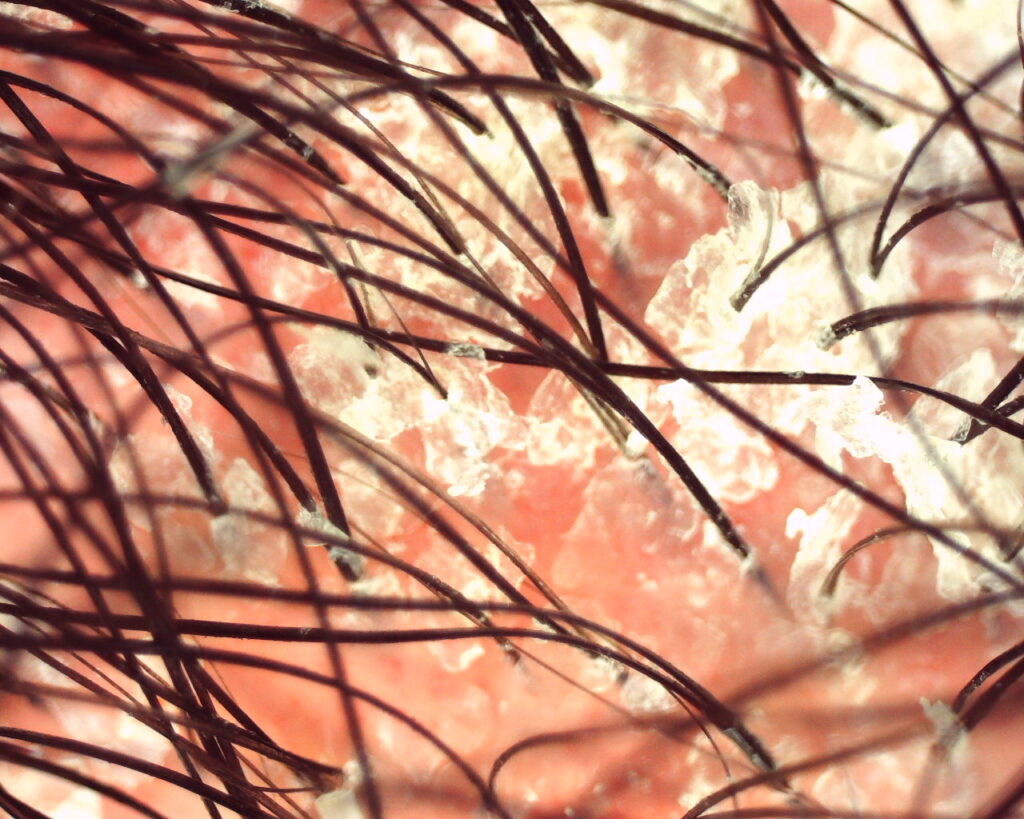

Em condições normais, a renovação dos queratinócitos ocorre em cerca de 28 dias. Na psoríase, esse processo pode ocorrer em apenas 3 a 5 dias, levando ao acúmulo de células imaturas na superfície cutânea. Esse fenômeno resulta nas placas típicas da doença, caracterizadas por eritema (vermelhidão), descamação espessa esbranquiçada ou prateada, inflamação persistente e prurido variável.

No couro cabeludo, as lesões podem aparecer de forma isolada ou ultrapassar a linha de implantação dos fios, formando o chamado sinal da coroa psoriática, um achado clínico clássico.

- placas eritematosas bem delimitadas com escamas espessas aderidas ao couro cabeludo

- Escamas geralmente mais secas e espessas do que as observadas na dermatite seborreica

- descamação visível nos fios

O diagnóstico é principalmente clínico e baseado na morfologia das lesões. A tricoscopia pode auxiliar mostrando achados como vasos pontilhados regulares, escamas espessas brancas e eritema difuso.